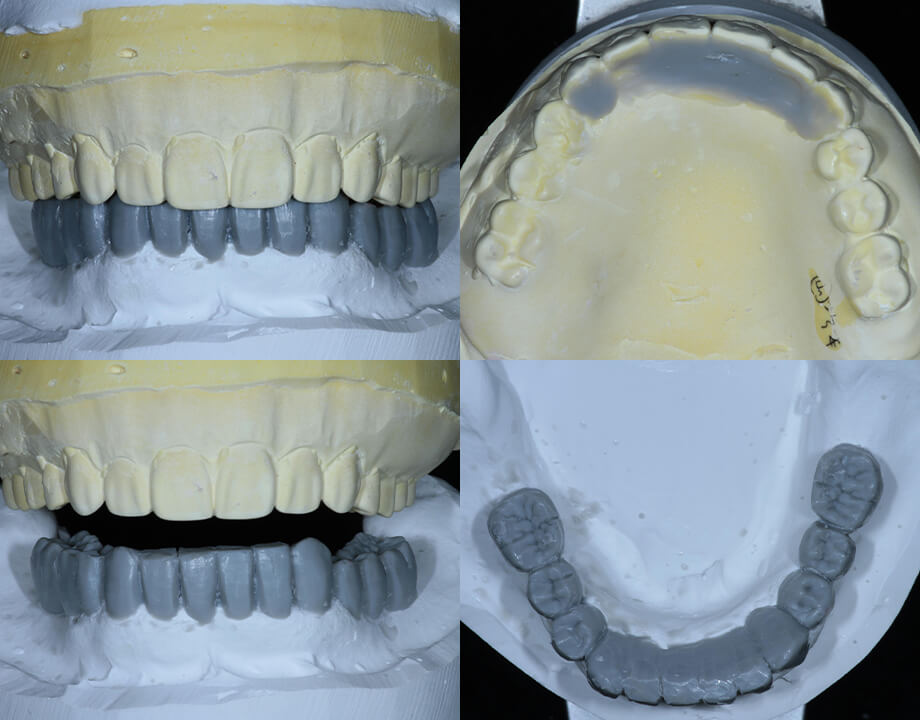

Case 07咬合再構成

アナログワックスアップ

→シュミレーション(ノーベルガイド)

→プロビジョナル(即時荷重)

→最終補綴物(ハイブリッドクラウン)

診断用ワックスアップ

全顎的な症例に限らず, 少数歯の症例においても,インプラントの埋入ポジションや矯正治療の有無など治療計画を立案する際に有効です。先生方々の治療計画のお役に立ちたいと思います。